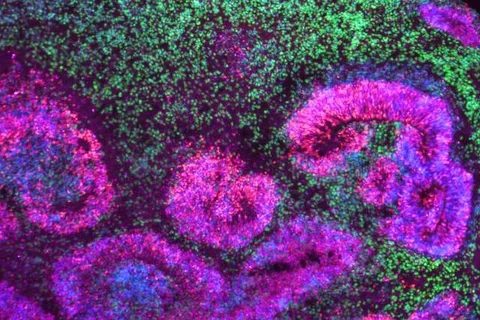

Pictured: Microscopy image of a cortical organoid, a stem cell-derived model that mimics the developing human brain. The circular rosettes are clusters of neural stem cells giving rise to neurons, shown in green. | Credit: Jose Soto/Bhaduri Lab

Bhaduri: Patricia created these resources that give us a much more streamlined view of the different parts of the brain and how they come about. But she didn’t stop there. In doing this work, she came up with a bunch of hypotheses about how brain development happens. She then used brain organoid models — 3D brain tissue grown from human stem cells — to test these hypotheses.